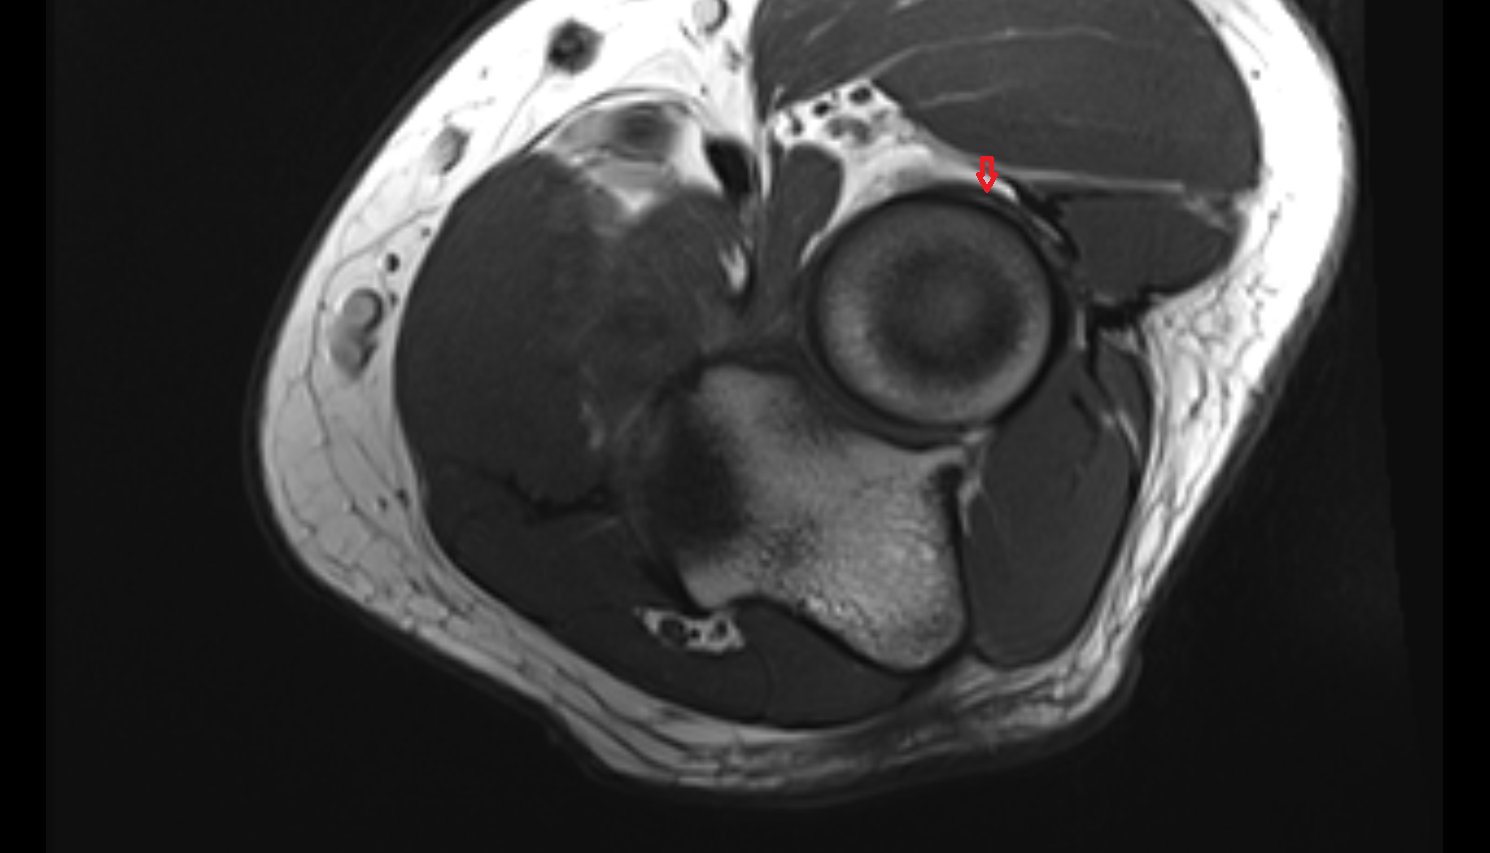

- Anterolateral ligament of knee